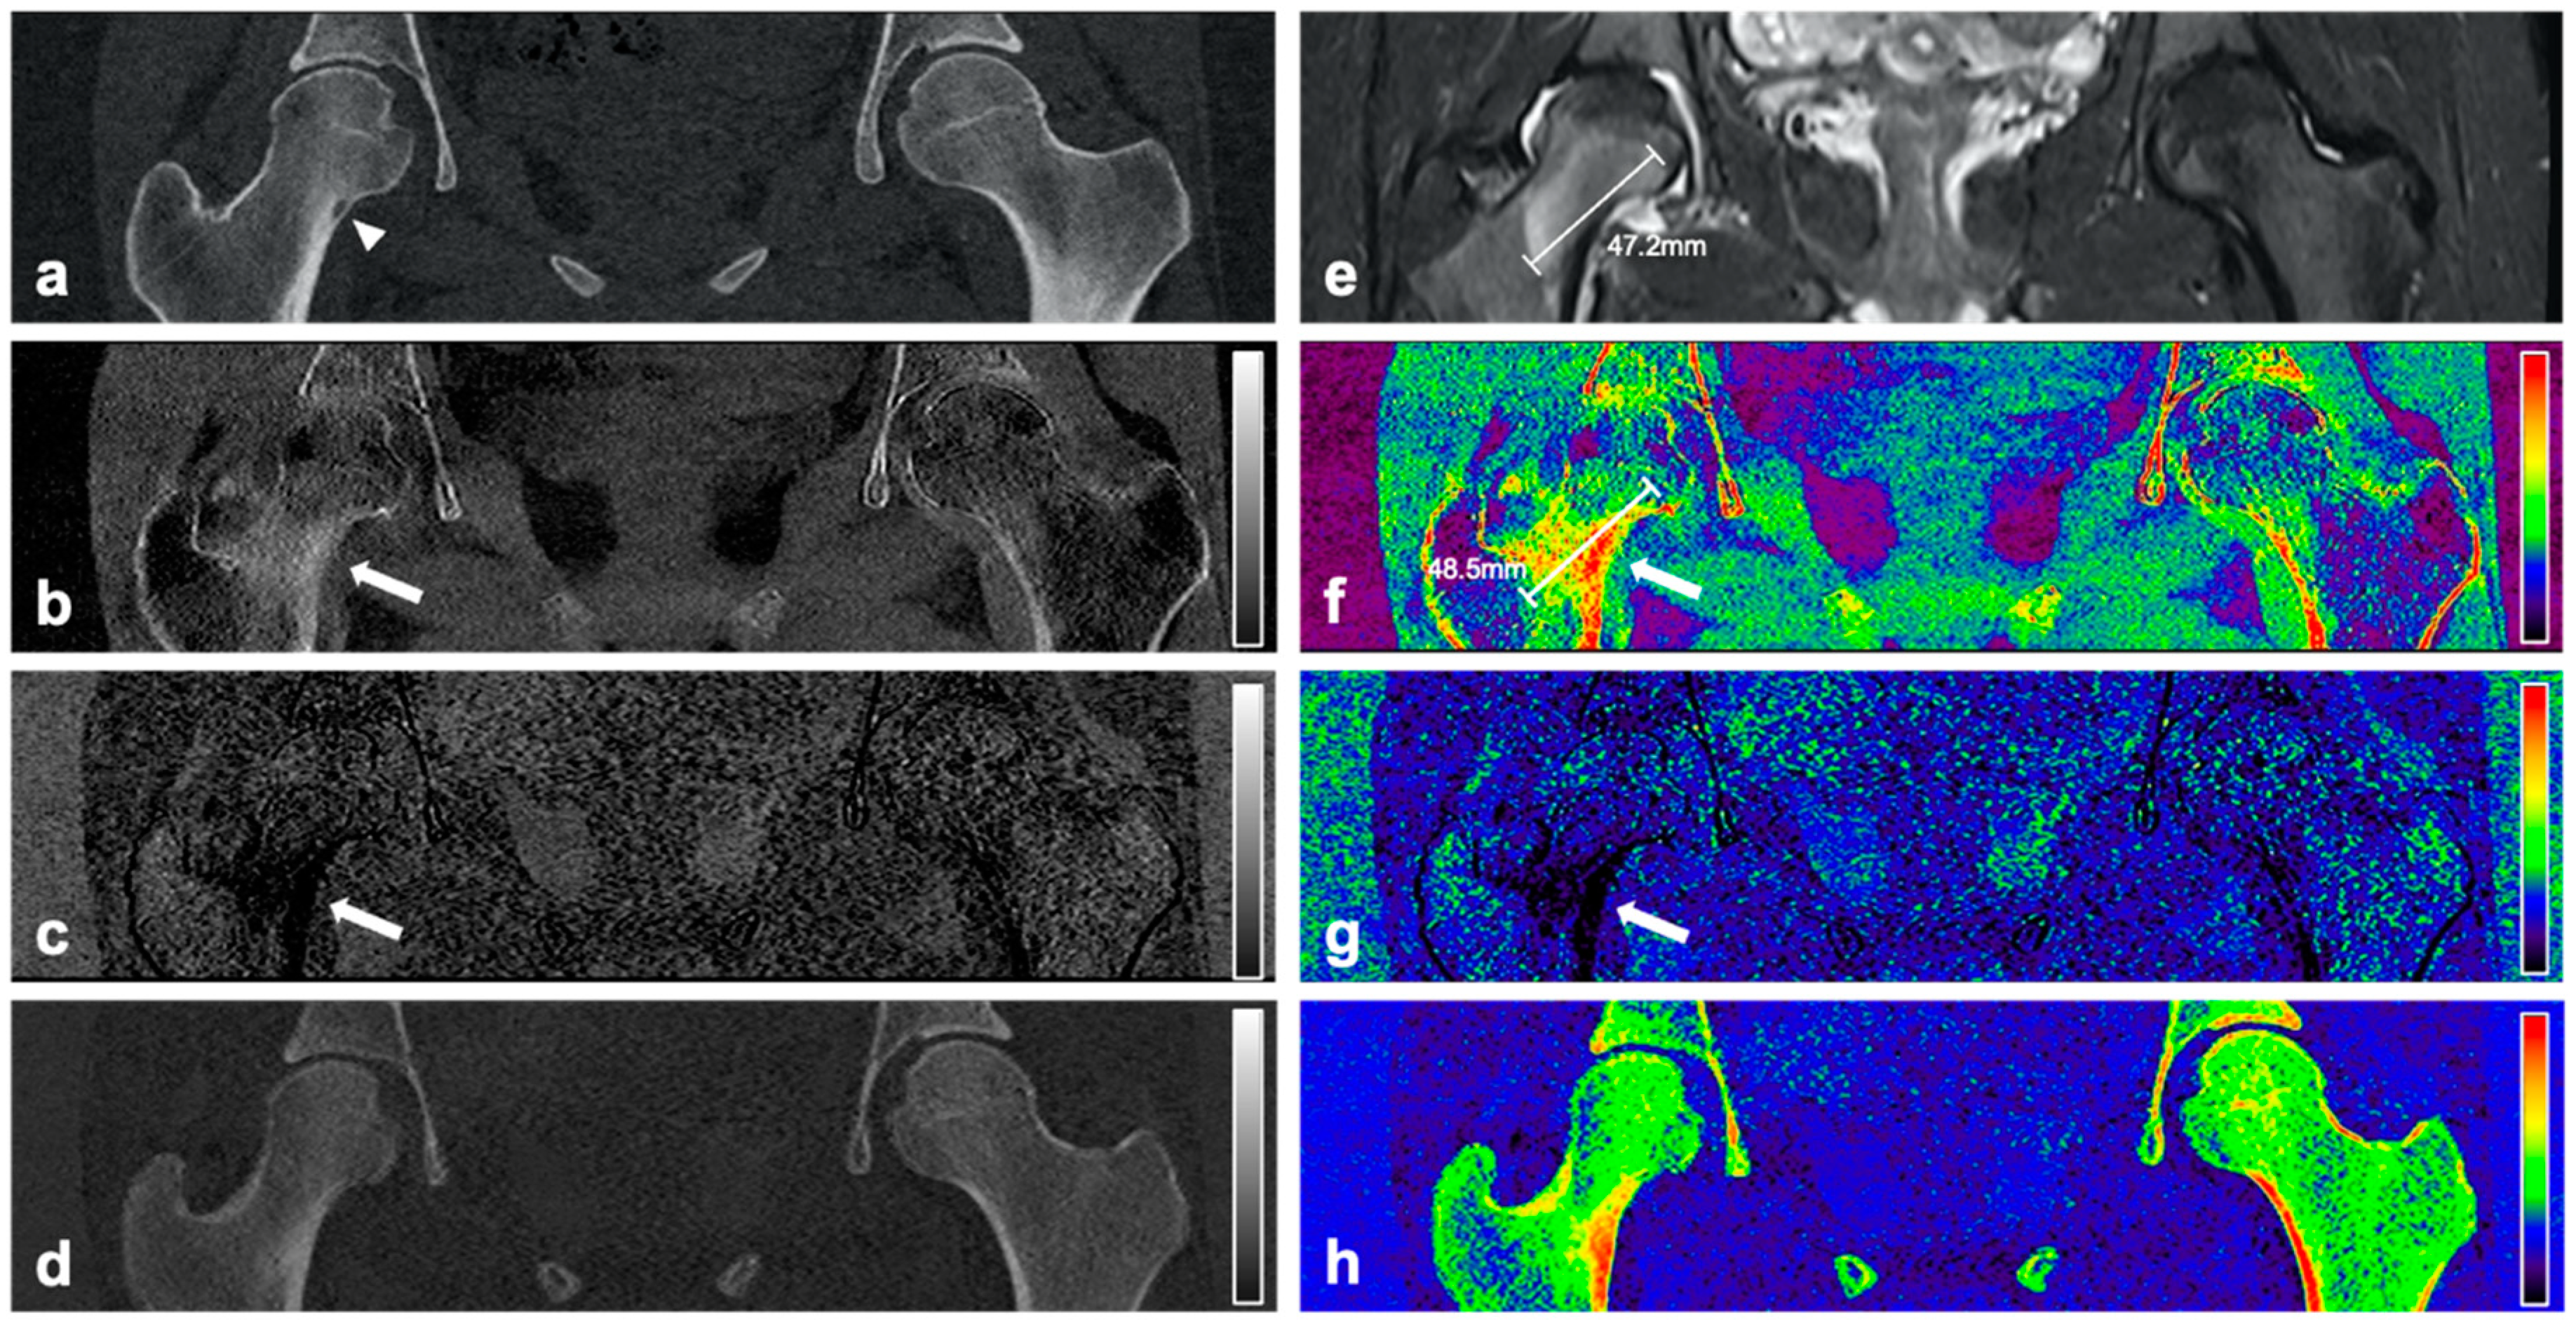

Figure 2. CT and MR images of an 18-year-old female patient with intracortical OO in the right femoral neck. Coronal reformation of the conventional CT examination (a) reveals the nidus in the right femoral neck with surrounding sclerosis (arrowhead). Material-specific volume fraction maps for red marrow/water (b), yellow marrow/fat (c), and hydroxyapatite (d), and respective color-coded overlays (fh) reveal an increase in water-specific volume fraction in the red-marrow map (b,f; arrow) and a decrease in fat-specific volume fraction in the yellow-marrow map (c,g; arrow) in the right femoral neck, compared to the respective area on the other side. The corresponding coronal STIR MR image confirms the presence of a half-moon shaped edema-equivalent signal alteration in the right femoral neck around (“half-moon sign” [13]) (e). Calipers indicate measurements of the extent of BME.